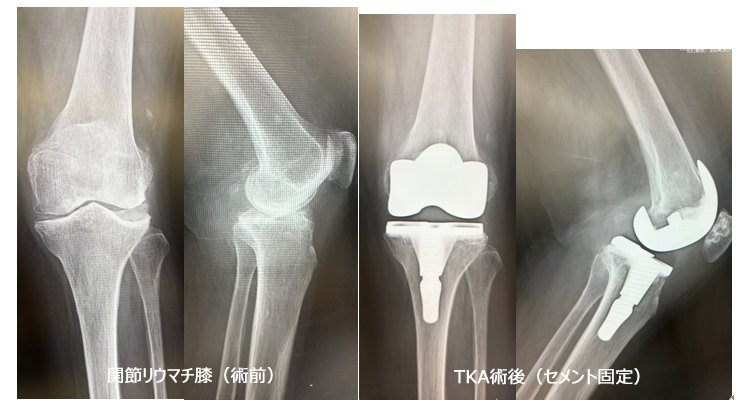

■ 人工膝関節全置換術(Total Knee Arthroplasty: TKA)

- 適応疾患: 主に変形性膝関節症(進行期)、関節リウマチによる膝関節の高度な破壊。

- 手術概要: 傷んだ膝関節の表面(大腿骨側、脛骨側、場合によっては膝蓋骨側)を削り、金属やポリエチレンでできた人工関節に置き換える手術です。関節全体を入れ替えることで、痛みを根本的に解消し、安定した歩行能力の回復を目指します。長期にわたる高い治療効果が期待できます。